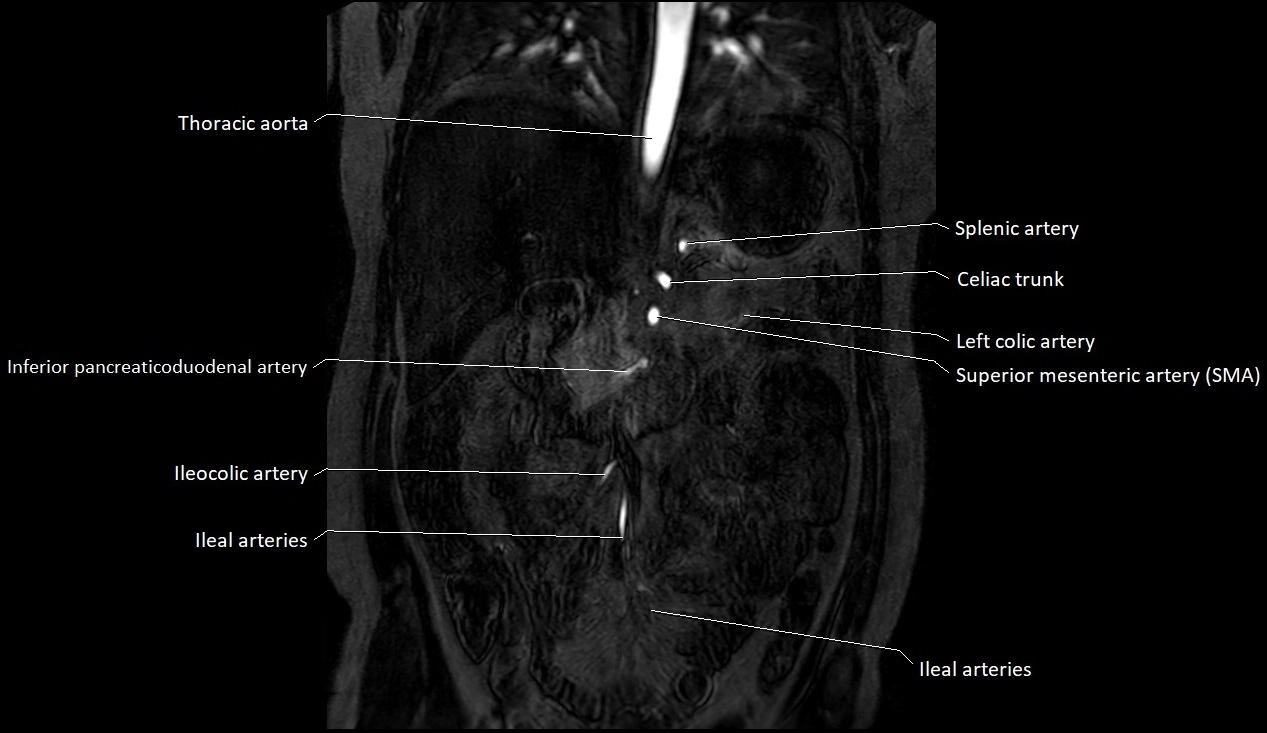

MRA (Magnetic Resonance Angiography):

• Contrast-enhanced MRA provides high-resolution imaging of the aorta and its branches

• Allows 3D reconstruction of visceral, parietal, and terminal branches

• Excellent for evaluating aneurysm size, dissection flap, stenosis, or preoperative planning

• Non-invasive alternative to conventional angiography

MRI images

image